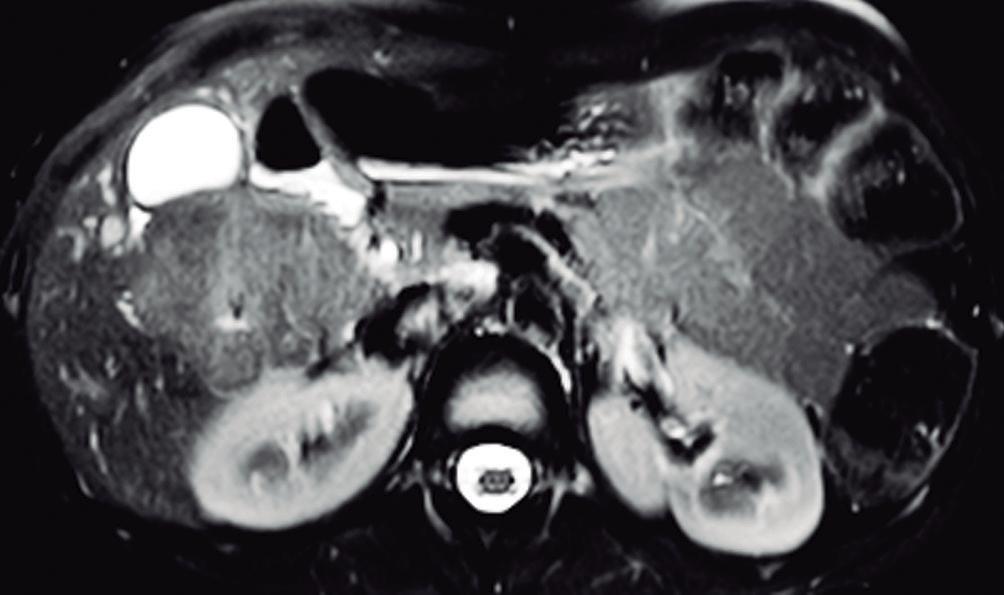

La HNF se manifiesta como uno o más nódulos (múltiple en aproximadamente 20%) de bordes netos y contornos lobulados. En la TCMC tiene densidad similar o apenas menor a la del parénquima adyacente. Si la cicatriz es visible (60%) en la TC es hipodensa. (Figura 3) En la RM su señal es isointensa o apenas hipo o hiperintensa en T1 e isointensa o un tanto hiperintensa en T2. (Figura 4) La cicatriz es hiperintensa en T2 (visible 80% en la RM), característica clave para diferen-

ciarla del hepatocarcinoma fibrolamelar (cuya cicatriz es hipointensa en T2 por fibrosis o por calcificación). Por otra parte, en algunos casos la diferenciación puede ser difícil ya que ambas son lesiones que ocurren en pacientes jóvenes con hígado sano y presentan similar aspecto y comportamiento poscontraste. Típicamente, la lesión realza intensamente en la fase arterial en forma homogénea y su densidad (o intensidad de señal en la RM) disminuye en fases sucesivas pero suele persistir levemente reforzada con respecto al hígado.4, 5 Los hepatocitos que forman la HNF son positivos para las proteínas transportadoras, característica que, sumada a la presencia de conductos biliares, explican el refuerzo de estas lesiones en la fase hepatobiliar en la RM con empleo de contraste hepatoespecífico. Esto permite establecer el diagnostico con un alto grado de certeza y alejar (sin descartar absolutamente) la posibilidad de un adenoma hepatocelular. El refuerzo puede ser isointenso con el parénquima, difusamente hiperintenso e hiperintenso en la periferia. (Figura 5) Dada la naturaleza benigna de la lesión, carece de riesgo de malignidad y el manejo de la HNF es conservador.8 Si el diagnóstico por imágenes es firme, no se requiere seguimiento. Si la lesión es sintomática, presenta características no típicas, es pediculada o exofítica, el caso debería ser sometido a discusión por un equipo multidisciplinario. La indicación de cirugía por la HNF es excepcional en casos sintomáticos o en raras circunstancias como sangrado o rotura.

A: En el domo hepático se observa en la secuencia T2 con supresión grasa un nódulo sólido que tiene una señal levemente hiperintensa con respecto al parénquima. Tiene bordes netos. Presenta una cicatriz central de mayor intensidad de señal. B: Imagen en secuencia T1 obtenida en fase arterial que demuestra el hiperrefuerzo de la lesión con excepción de su cicatriz central. C: Imagen en fase portal en la que se puede apreciar que la lesión sólo conserva una leve hiperintensidad con respecto al parénquima. Persiste sin refuerzo la cicatriz central. D: Imagen obtenida en fase de equilibrio. La lesión sólo muestra una hiperintensidad sutil y se puede apreciar el refuerzo tardío de la cicatriz, típico de la HNFl.

Lesiones benignas localizadas en el hígado desde la mirada de las imágenes Mariano Volpacchio Figura 4. HNF en la RM